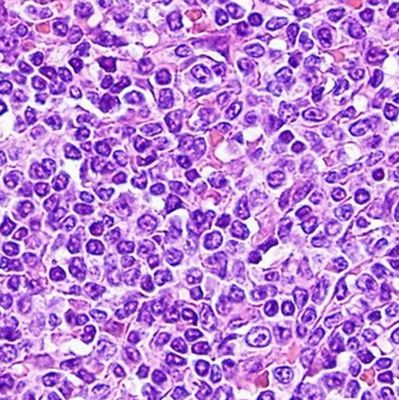

Микропрепараты: Лимфогранулематоз и Нодулярный Склероз

Раздел: Секреты мастерства